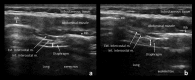

Neuromuscular ultrasound (NMUS) is becoming a standard element in the evaluation of peripheral nerve and muscle disease. When obtained simultaneously to electrodiagnostic studies, it provides dynamic, structural information that can refine a diagnosis or identify a structural etiology. NMUS can improve patient care for those with mononeuropathies, polyneuropathy, motor neuron disease and muscle disorders. In this article, we present a practical guide to the basics of NMUS and its clinical application. Basic ultrasound physics, scanning techniques and clinical applications are reviewed, along with current challenges.